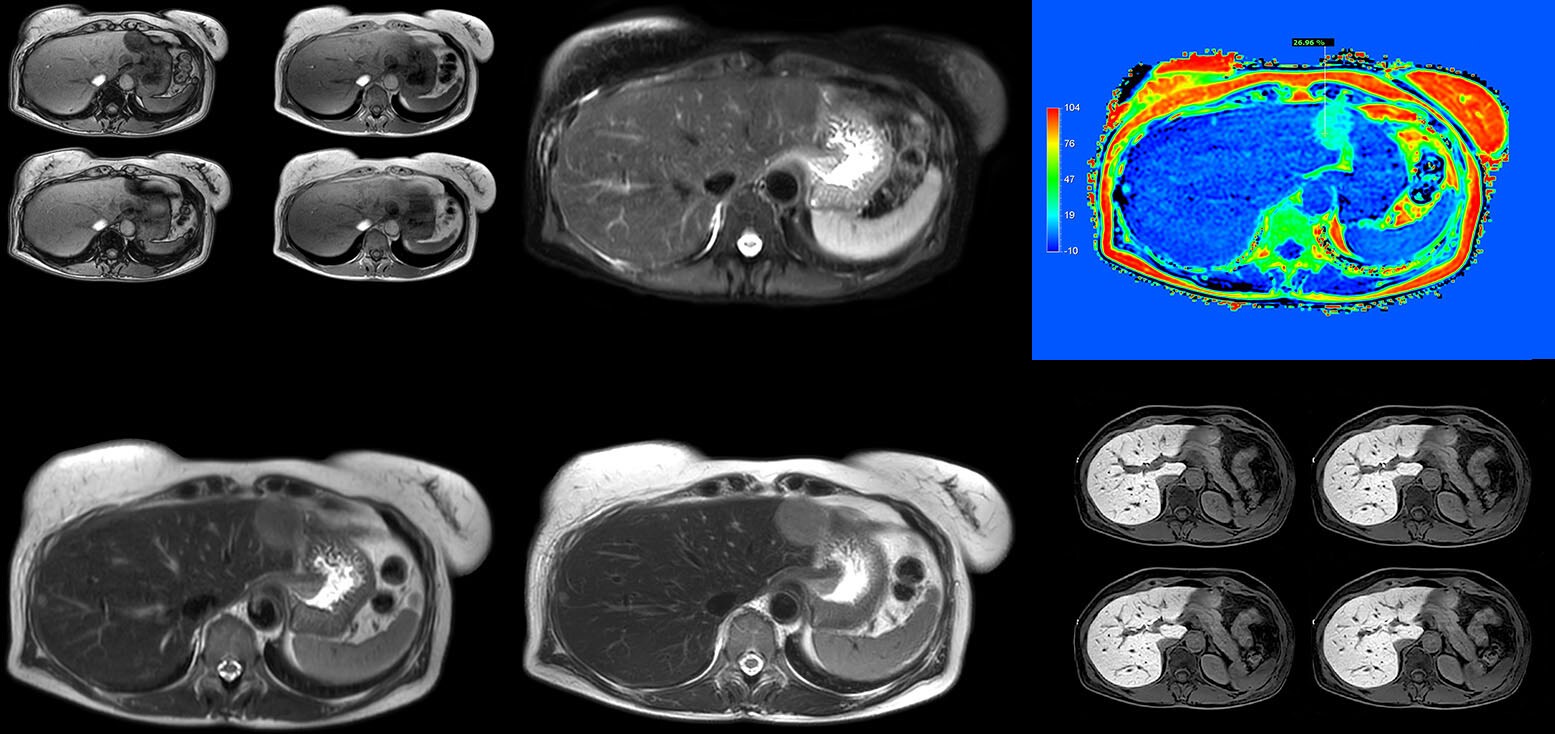

Dr. Kukuk’s liver exam begins with T2-weighted imaging, single shot and with fat suppression. “We always perform diffusion weighted imaging (DWI) with four b-values (0, 50, 250, 800) for lesion characterization, for monitoring after therapies, and for visualization of small lesions. Before giving contrast we routinely use the mDIXON Quant fat quantification sequence. Then we use dynamic e-THRIVE with an in-plane spatial resolution of 1.5 mm and high temporal resolution in just four breathholds of 13.1 seconds.” “Contrast enhancement is important to help us characterize lesions, for follow up in oncology patients and to inform clinicians when deciding on possible changes in the therapeutic regimen,” Dr. Kukuk explains. “Because we use liver-specific contrast agents we can obtain the T2-weighted images after the dynamic, to bridge the waiting time needed with these contrast agents. Just before the patient leaves the scanner we acquire another e-THRIVE in the axial plane and one or two coronals.”

“Using MultiVane XD motion correction, we are now able to acquire high spatial resolution T2-weighted images without seeing relevant motion,” says Dr. Kukuk. “It’s a great technique to obtain high spatial resolution images of the pancreas or the liver, as well as the surrounding organs and tissues. MultiVane XD can be combined with dS SENSE parallel imaging, allowing us to reduce specific absorption rates (SAR), acquire high spatial resolution in short acquisition times, and at the same time reduce artifacts caused by motion in adjacent tissues and organs.”

“In comparison to single shot T2-weighted TSE, this approach with MultiVane XD motion suppression provides higher spatial resolution. In addition, it is especially valuable in patients who cannot hold their breath or have some disabilities. My impression is that this sequence has the potential to substitute for, or even replace, the T2-weighted single shot sequence in our liver exams, because of good and consistent delineation of small lesions.”

“We have performed a study comparing mDIXON Quant fat percentages with results from histopathology. The correlation with different histologic methods was very good and also the correlation with MR spectroscopy was far above 0.9 – a nearly perfect correlation,” says Dr. Kukuk.

“Fatty liver disease is a common condition. Studies found a prevalence of non-alcoholic fatty liver disease in up to 44% in the general European population [1]. Liver fat cannot be quantified by ultrasound or CT, so biopsy has been the way to quantify fatty liver disease so far,” says Dr. Kukuk. “mDIXON Quant now allows non-invasive quantification of liver fat, which is valuable for both diagnosis and follow-up during dietary changes or therapy, for instance in hepatitis C.”

“The mDIXON Quant fat fraction maps provide quantitative information and also anatomical detail. The sequence is fast, usually taking about 16 seconds, which is just a breath hold for most patients. It definitely improves our efficiency.”